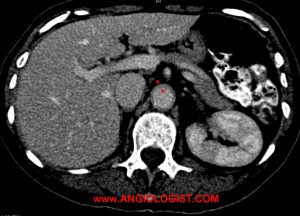

- Computed tomography – CT with contrast can be useful both for the diagnosis of arterial inflammation and for the diagnosis of possible vascular complications of giant cell arteritis.

As I wrote above, aneurysms can be a complication of the inflammatory process. Surgical resection of these aneurysms has been described with good overall results. The aneurysms may be a remnant of past disease or present during active phases. If the disease is active, surgery should be postponed, if possible, until the inflammation cools off. Anti-inflammatory medication is sometimes added after surgery The timing of this treatment after surgery is unclear, as early treatment may interfere with healing, while late treatment may expose patients to further complications.